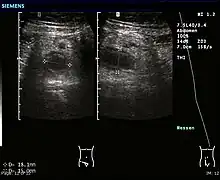

Ultrasound

Ultrasound image of acute appendicitis

Abdominal ultrasonography, preferably with doppler sonography, is useful to detect appendicitis, especially in children. Ultrasound can show the free fluid collection in the right iliac fossa, along with a visible appendix with increased blood flow when using color Doppler, and noncompressibility of the appendix, as it is essentially walled-off abscess. Other secondary sonographic signs of acute appendicitis include the presence of echogenic mesenteric fat surrounding the appendix and the acoustic shadowing of an appendicolith.[55] In some cases (approximately 5%),[56] ultrasonography of the iliac fossa does not reveal any abnormalities despite the presence of appendicitis. This false-negative finding is especially true of early appendicitis before the appendix has become significantly distended. Also, false-negative findings are more common in adults where larger amounts of fat and bowel gas make visualizing the appendix technically difficult. Despite these limitations, sonographic imaging with experienced hands can often distinguish between appendicitis and other diseases with similar symptoms. Some of these conditions include inflammation of lymph nodes near the appendix or pain originating from other pelvic organs such as the ovaries or Fallopian tubes. Ultrasounds may be either done by the radiology department or by the emergency physician.[57]